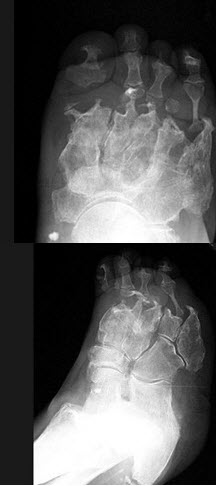

20、单项选择题

女,78岁,长期慢性手足畸形,无冷热、痛感,结合图像,最可能的诊断是()

A.骨麻风病

B.骨梅毒

C.骨结核

D.痛风

E.类风湿关节炎